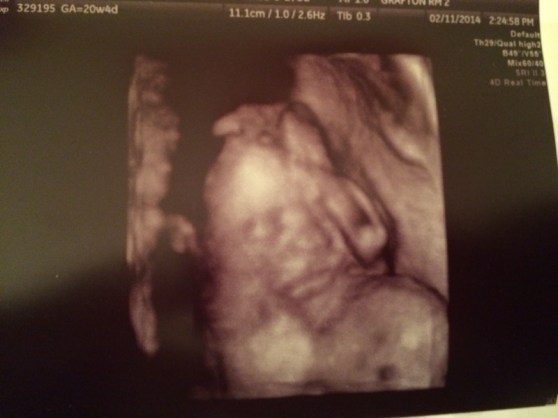

My favorite little face pic. She’s just so precious with her little hand up by her face. I can’t wait to kiss that little face.

This one is a big blur… but there’s that little hand again.